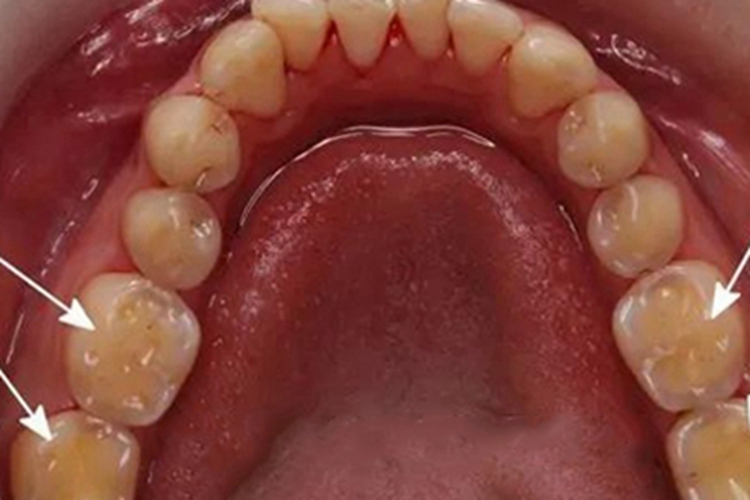

牙齿出现酸蚀症时,可有骨质缺损,牙冠表面有许多坑洼,大小不一,使之不平整,坑洞可随病情进展进一步扩大。

酸蚀症通常由饮食中的酸性物质,如柠檬汁、碳酸饮料等,以及胃酸或唾液中的酸性物质,如胃酸逆流引起,这些酸性物质可以溶解牙齿釉质中的钙和磷离子,使牙齿表面变得脆弱。长期暴露于酸性环境下,牙齿的釉质会逐渐溶解,形成凹槽状的缺损,有坑。